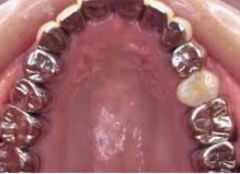

1・銀歯から始まる 歯を失う連鎖

成人のおよそ80%の方に、銀歯が口の中に入っています。

虫歯になる→歯を削る→型を取る→銀歯を入れる→虫歯が再発→大きく歯を削る→神経を抜く→

金属の土台を入れて銀歯を被せる→歯根破折を起こす→抜歯になる